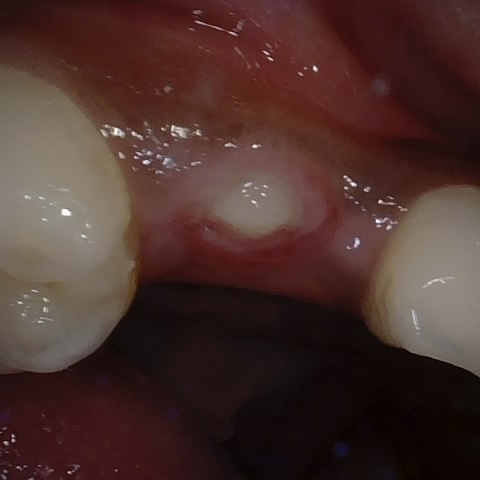

Annotated as "Good"

Original Image Rendering Image